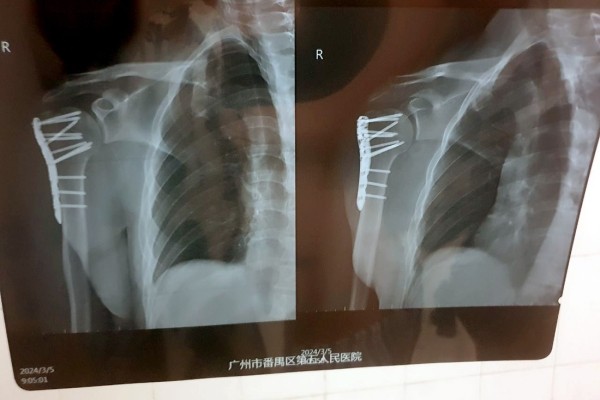

Операцию все-таки пришлось сделать. По словам врачей, в противном случае кости срастались бы очень долго.

— Все это заняло около двух часов. Процесс не был приятным, так как я был в сознании и ощущал все манипуляции, проводимые на костях моего плеча, включая сверление, например. Была установлена пластина, которая зафиксировала поврежденные кости в правильном положении. После операции побочных эффектов не было, однако в течение еще шести часов врачи подключали различные датчики для контроля состояния. Все это время нельзя было есть и пить. А рука ощущалась как кусок бревна, — вспоминает читатель.

— Китайские врачи проделали по-настоящему хорошую работу. Это подтвердил знакомый белорусский хирург, взглянув на мои послеоперационные снимки. Думаю, не последнюю роль в этом сыграло и то, что я иностранец: мне показалось, что врачи особенно старались сделать все по высшему разряду. Также это хороший пример того, что надо смотреть не на вывеску больницы. Главное — это именно врачи и их отношение к своей работе, — считает молодой человек.

Белоруса выписали из больницы спустя три дня после операции. Впереди длительная реабилитация и еще одна операция — для того, чтобы изъять из плеча металлическую пластину.